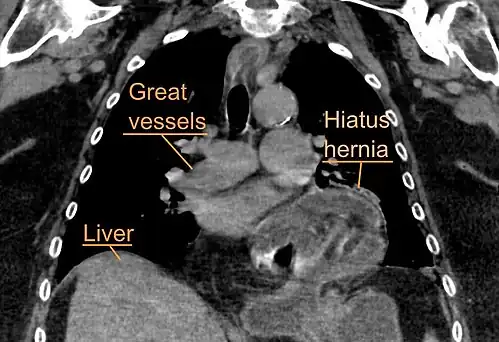

A large hiatal hernia as seen on CT imaging